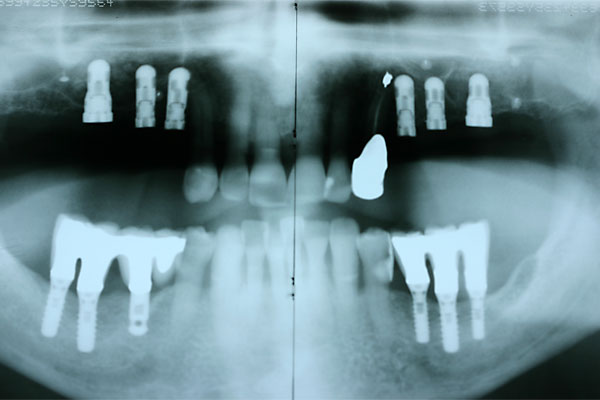

Fall: festsitzender Zahnersatz im Oberkiefer auf 8 Implantaten

FOTO Ausgangsröntgenbild |